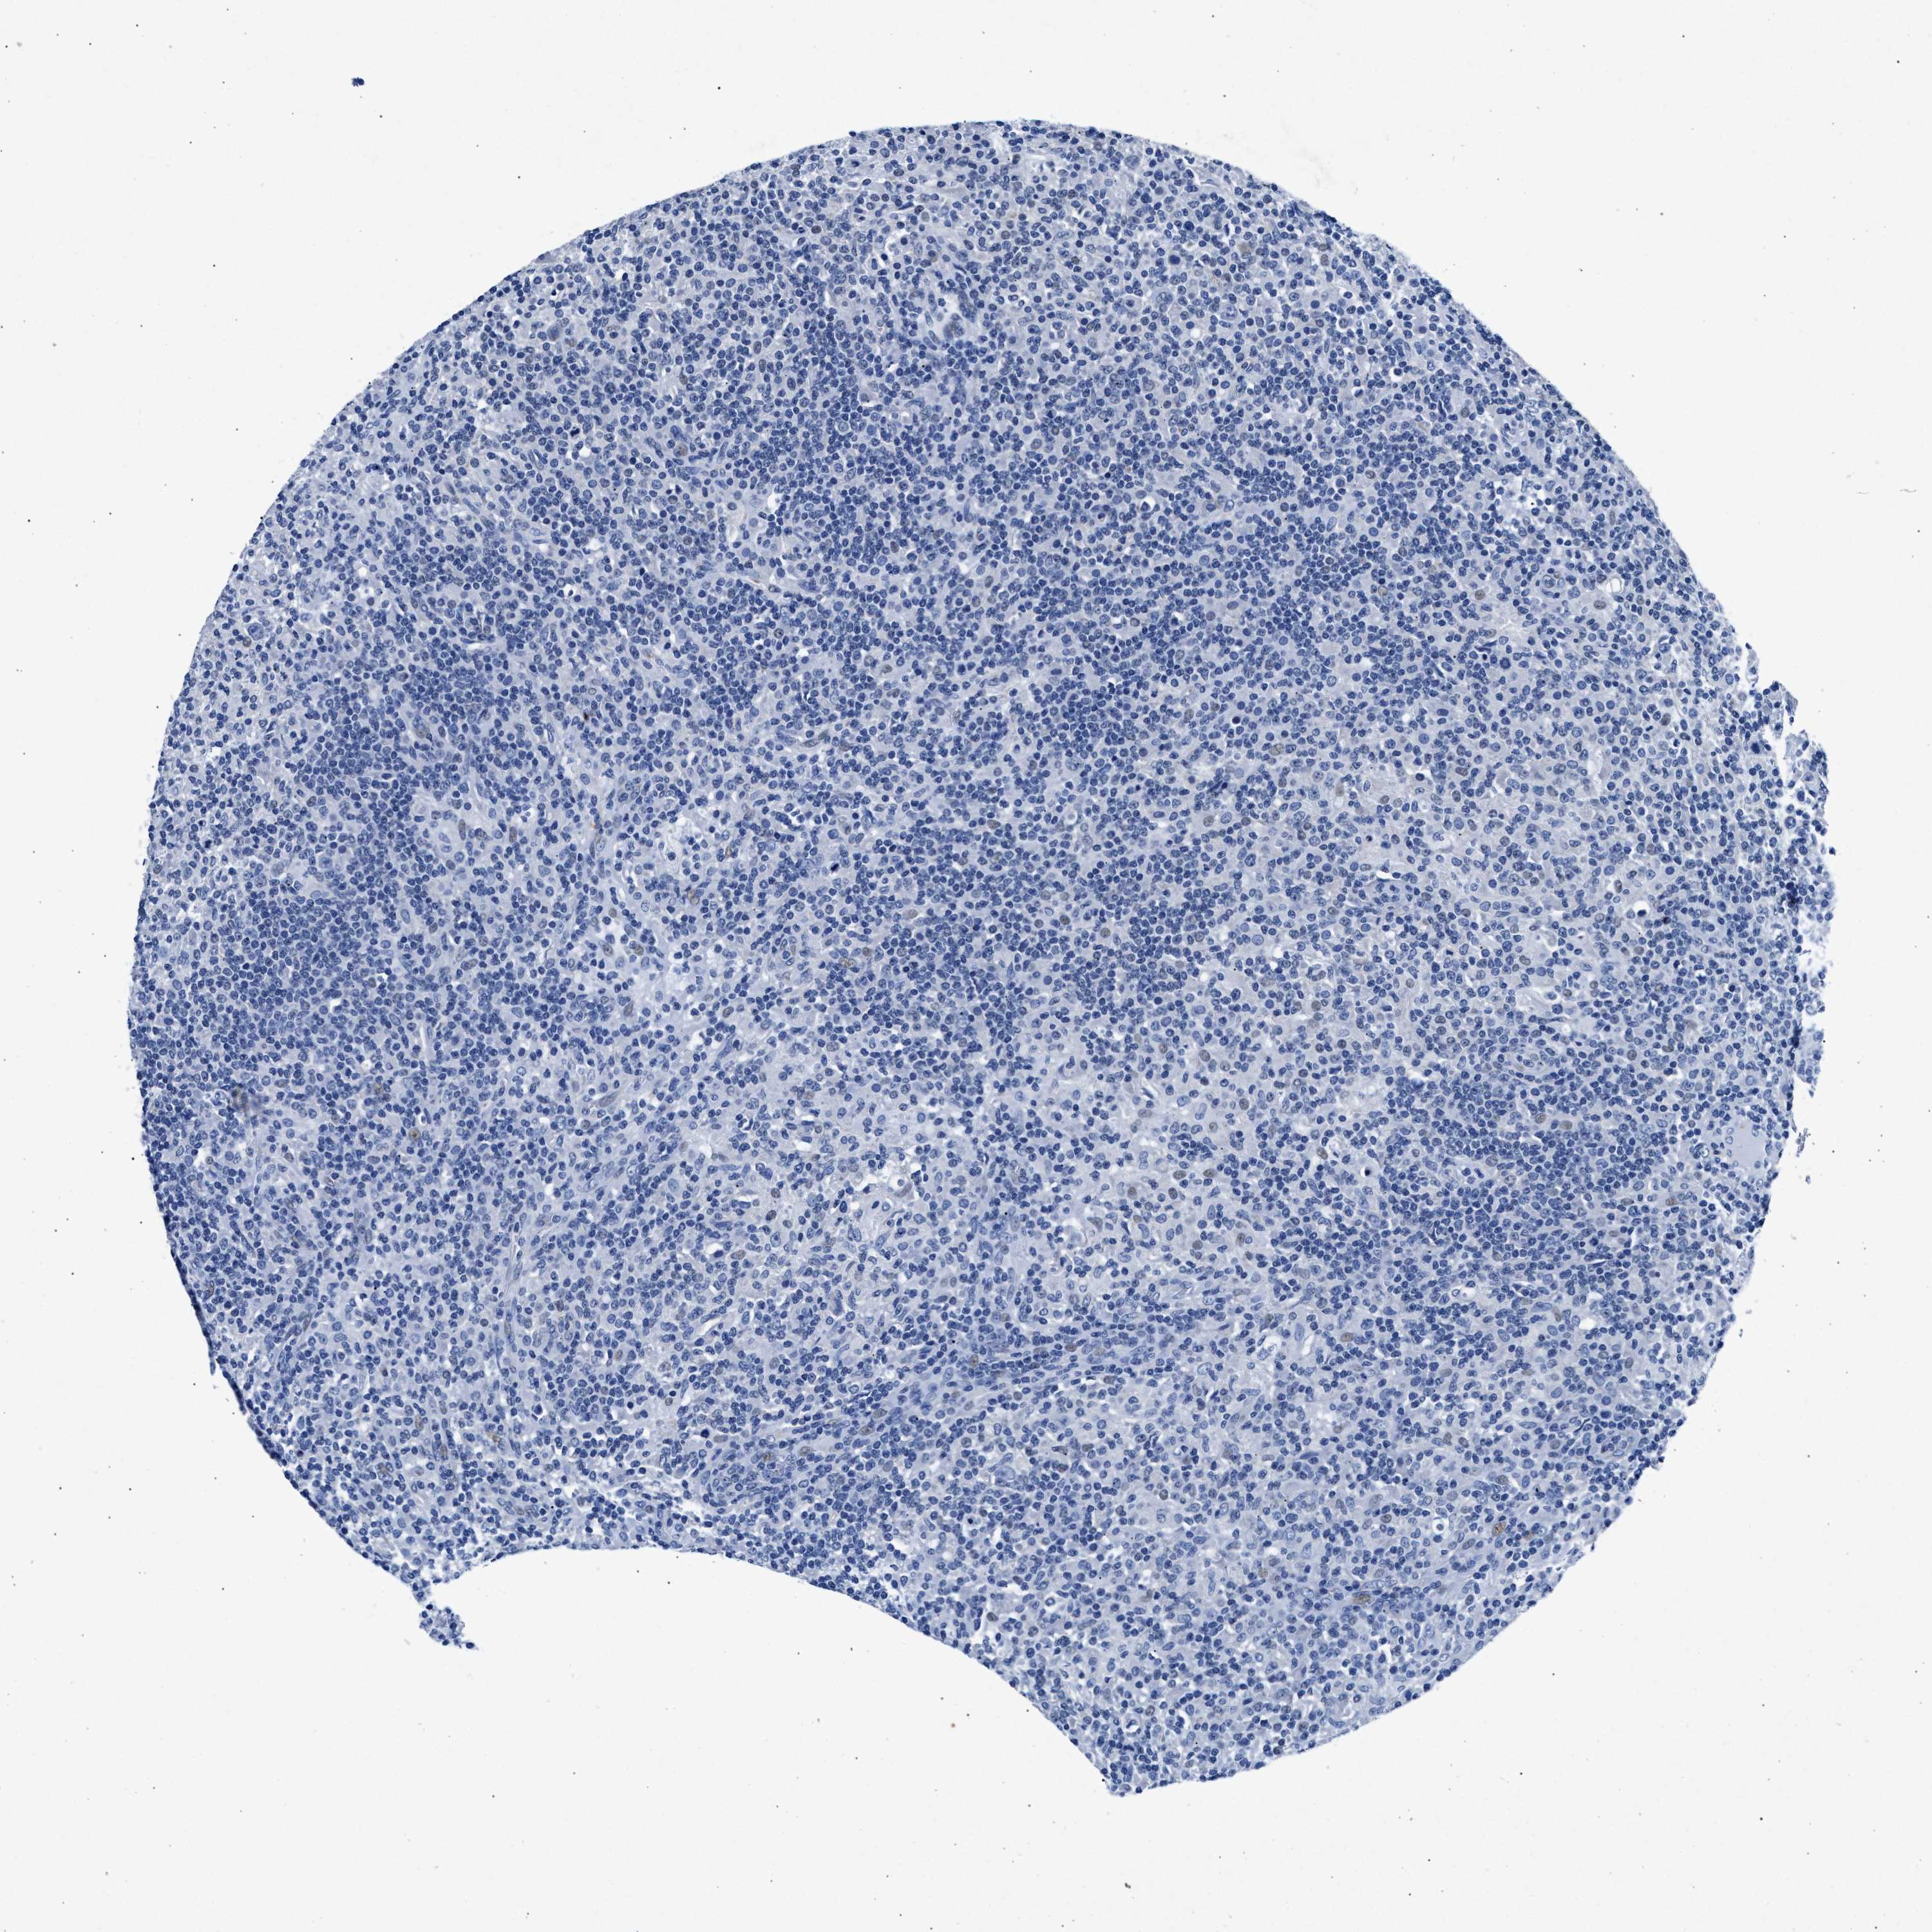

CANCER LYMPHOMA Show tissue menu

LYMPHOMA - Protein expressioni

A mouse-over function shows sample information and annotation data. Click on an image to view it in a full screen mode. Samples can be filtered based on level of antibody staining by selecting one or several of the following categories: high, medium, low and not detected. The assay and annotation is described here.

Each image is clickable and will lead to virtual microscopy that enables deeper exploration of all samples and also displays staining intensity scores, fraction scores and subcellular localization as well as patient and tissue information for each sample.

Antibody HPA039061

Antibody HPA039062

Antibody CAB015442

Antibody CAB022600

Hodgkin's disease, NOS

Malignant lymphoma, non-Hodgkin's type, High grade

Malignant lymphoma, non-Hodgkin's type, Low grade